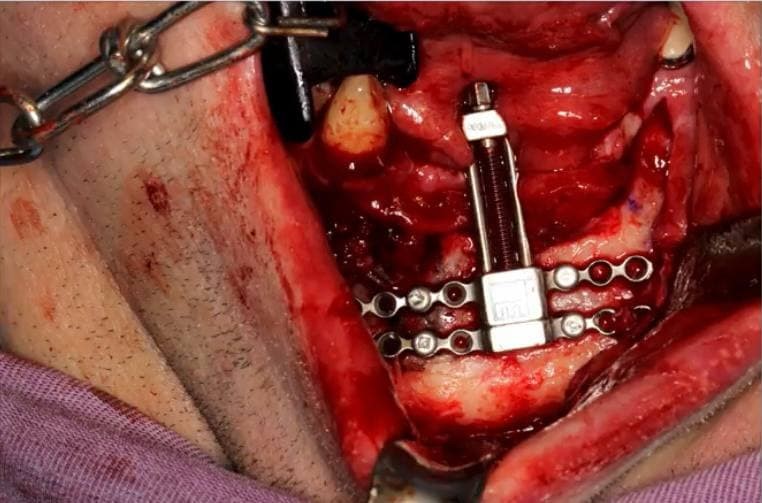

Начинаем мы с того, что крепим дистрактор в подбородочный отдел.

Это как аппарат Илизарова, только на челюсти.

И каждый день его подкручиваем, чтобы пластина шла всё выше и выше. Серьёзно, вращаем специальным устройством вроде высокотехнологичной отвёртки каждый день. Кость «тянется» под давлением конструкции.